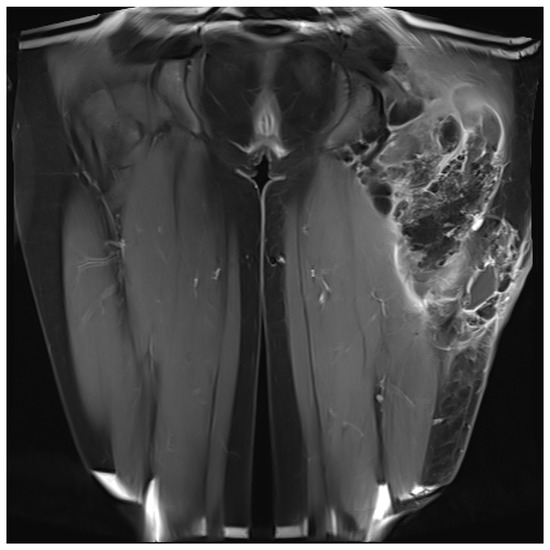

The indication for surgical treatment was a persistent pathology of the musculoskeletal system in the lower extremity. Either because conservative therapy was not successful, or ulcerations were present. Conservative therapy included sufficient medical treatment for RAD and physiotherapeutic therapy and provision of assistive devices where necessary. When surgical treatment was indicated, a preoperative evaluation was performed. Imaging with CT, MRI in conjunction with angiography, and lymphography were used (Figure 1 and Figure 2). Surgeries were performed under steady-state conditions and single-shot antibiotics. The supplies were primarily not joint-related but addressed periarticular tissue.

The patients presented with calcifications in the large muscle groups (gluteal, quadriceps, and gastrocnemius muscles). These spread to tendons and subcutaneous tissue (Figure 2). Four patients had previously undergone trial biopsies, and three of these four subsequently developed a fistula with secondary bacterial colonization of the wound. Surgical therapy was based on the extent of the lesions and consisted of the most radical exstirpation of the affected tissue. In these cases, solid tumor-like calcifications were usually found adjacent to pasty changes (Figure 3).

Figure 2. Calcinosis tumor with solid and liquid portions, MRI T2 Sequence. ©UKGM Giessen.